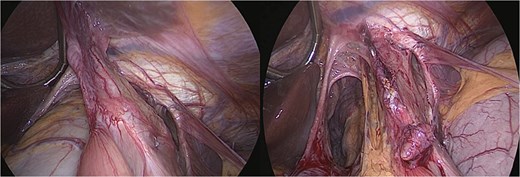

An urgent laparoscopic exploration was performed, revealing a large hiatal defect with exposure of the posterior mediastinum and aorta. The proximal portion of the gastric remnant remained within the abdominal cavity, while the distal remnant and duodenum had herniated into the thoracic cavity and exhibited rotation. The remnant stomach was found to be significantly distended and edematous, containing ~3 l of coffee-ground fluid. Additionally, the entire gastric pouch and gastrojejunal anastomosis were discovered herniated within the chest (Fig. 2).

Intraoperative view—large hiatal defect before and after reduction herniated viscera.